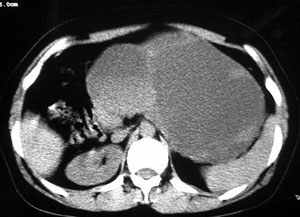

强化片

这个要问下病史,如无胰腺炎病史首先考虑胰腺体尾部的粘液囊腺瘤,此瘤太大,有分叶和实性成份要考虑恶性或潜在恶性可能,后两幅主动脉左旁结节状强化影止于左肾静脉,考虑双下腔静脉,请结合往下的片

以下是引用守望可可西里在2006-8-30 10:57:00的发言:[br][br] 定位:胰腺体尾部。[br] 定性:胰腺囊腺癌可能性大。[br] 理由:胰腺体尾部呈多囊状分叶,部分病灶与前腹壁粘连,且下部形态不规则,毛糙不整、凸凹不平。囊壁厚薄不一致,多个大小不等壁结节突入,囊壁及壁结节明显不均匀强化。偏右侧囊内见液-液平面样相对高密度,呈与壁结节类似强化。性质:1.出血?2.壁结节?

以下是引用duguo在2006-8-30 12:13:00的发言:[br]支持胰腺囊腺癌诊断,建议穿刺活检.